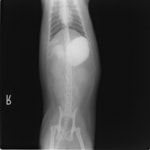

9歳 チワワ 4.8kg

主訴:2日前の夜に桃の種を飲み込んだとのこと。元気・食欲に問題はなく、嘔吐などの消化器症状もみられなかった。誤飲した当日に他院にて催吐処置を試みたが、吐き戻さなかったとのこと。

単純レントゲン検査:明らかな異常所見なし

消化管バリウム造影レントゲン検査:胃内にて異物の存在を疑う異常所見を認めた。

造影直後

内視鏡検査:内視鏡下にて、バスケット鉗子を用いて胃内異物を摘出。

異物内容:桃の種 (約4cm大 写真上)、とうもろこしの芯 (約2.5cm大 写真下)

本症例は、床に落としてしまった桃の種を誤飲していました。動物の体格に対して異物が非常に大きく、開腹手術となる可能性があった症例でした。また、桃の種と一緒に出てきたとうもろこしの芯は、日々のおやつとして与えていたものということでした。とうもろこしの芯は非常に硬く、小さく切って与えても消化されず、長期間胃内に残ってしまうことや腸閉塞の原因となる為、注意が必要です。